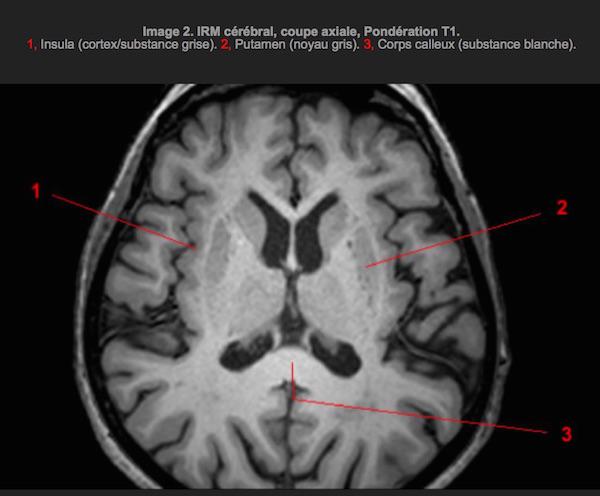

Au cours de l’examen, les chercheurs ont observé leur cerveau à l’IRM (imagerie par résonance magnétique). Dans un premier temps, ils ont regardé sa structure et ont découvert plusieurs anomalies au niveau de la matière grise et de la substance blanche chez les sujets psychopathes. La première est impliquée dans le traitement de l’information et les processus cognitifs, quand la seconde coordonne la transmission de l’information entre les différentes parties du cerveau.

Cliché IRM d'un cerveau - Source : info-radiologie.ch

« Nous avons observé un plus faible niveau de matière grise dans le cortex préfrontal antérieur et dans des zones des lobes frontaux », expliquent les auteurs de l’étude. Ces zones sont associées à l’empathie, au traitement des émotions prosociales comme la culpabilité, l’embarras, le raisonnement moral. Quant à la substance blanche, d’autres anomalies ont été révélées au niveau du cortex préfrontale médian et du cortex cingalaire postérieur, tous deux impliqués dans l’apprentissage au moyen de récompenses et de punitions.